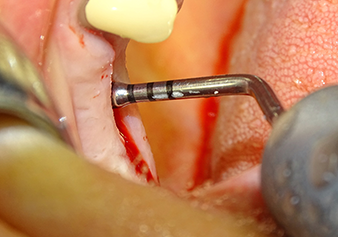

Implant bed preparation and augmentation

Following an intermediate check (Fig. 4) a further preparation step was performed (Fig. 5). Afterwards, the hydraulic Z35P instrument was used to lift the membrane to the desired position (Fig. 6 and 7). This was followed by further piezosurgical preparation of the implant bed, concluded with a rotary bur and shoulder milling cutter up to the implant diameter of 4.8 mm. Before the implant was inserted, the augmentation material (particle size approx. 0.8-1.6 mm) was introduced underneath the Schneiderian membrane (Fig. 8).

The implant bed is widened to 3.0 mm with the I3A instrument

Fig.5: In the next step, the implant bed is widened to 3.0 mm with the I3A instrument (power 100%, coolant 80%). The depth marks reliably prevent the preparation from going too deep.

The Schneiderian membrane is stretched 1.5-2 mm above the bony access

Fig.4: Intermediate check: The bone height above the maxillary sinus floor is approx. 4 mm palatal and buccal; the Schneiderian membrane is stretched 1.5-2 mm above the bony access.